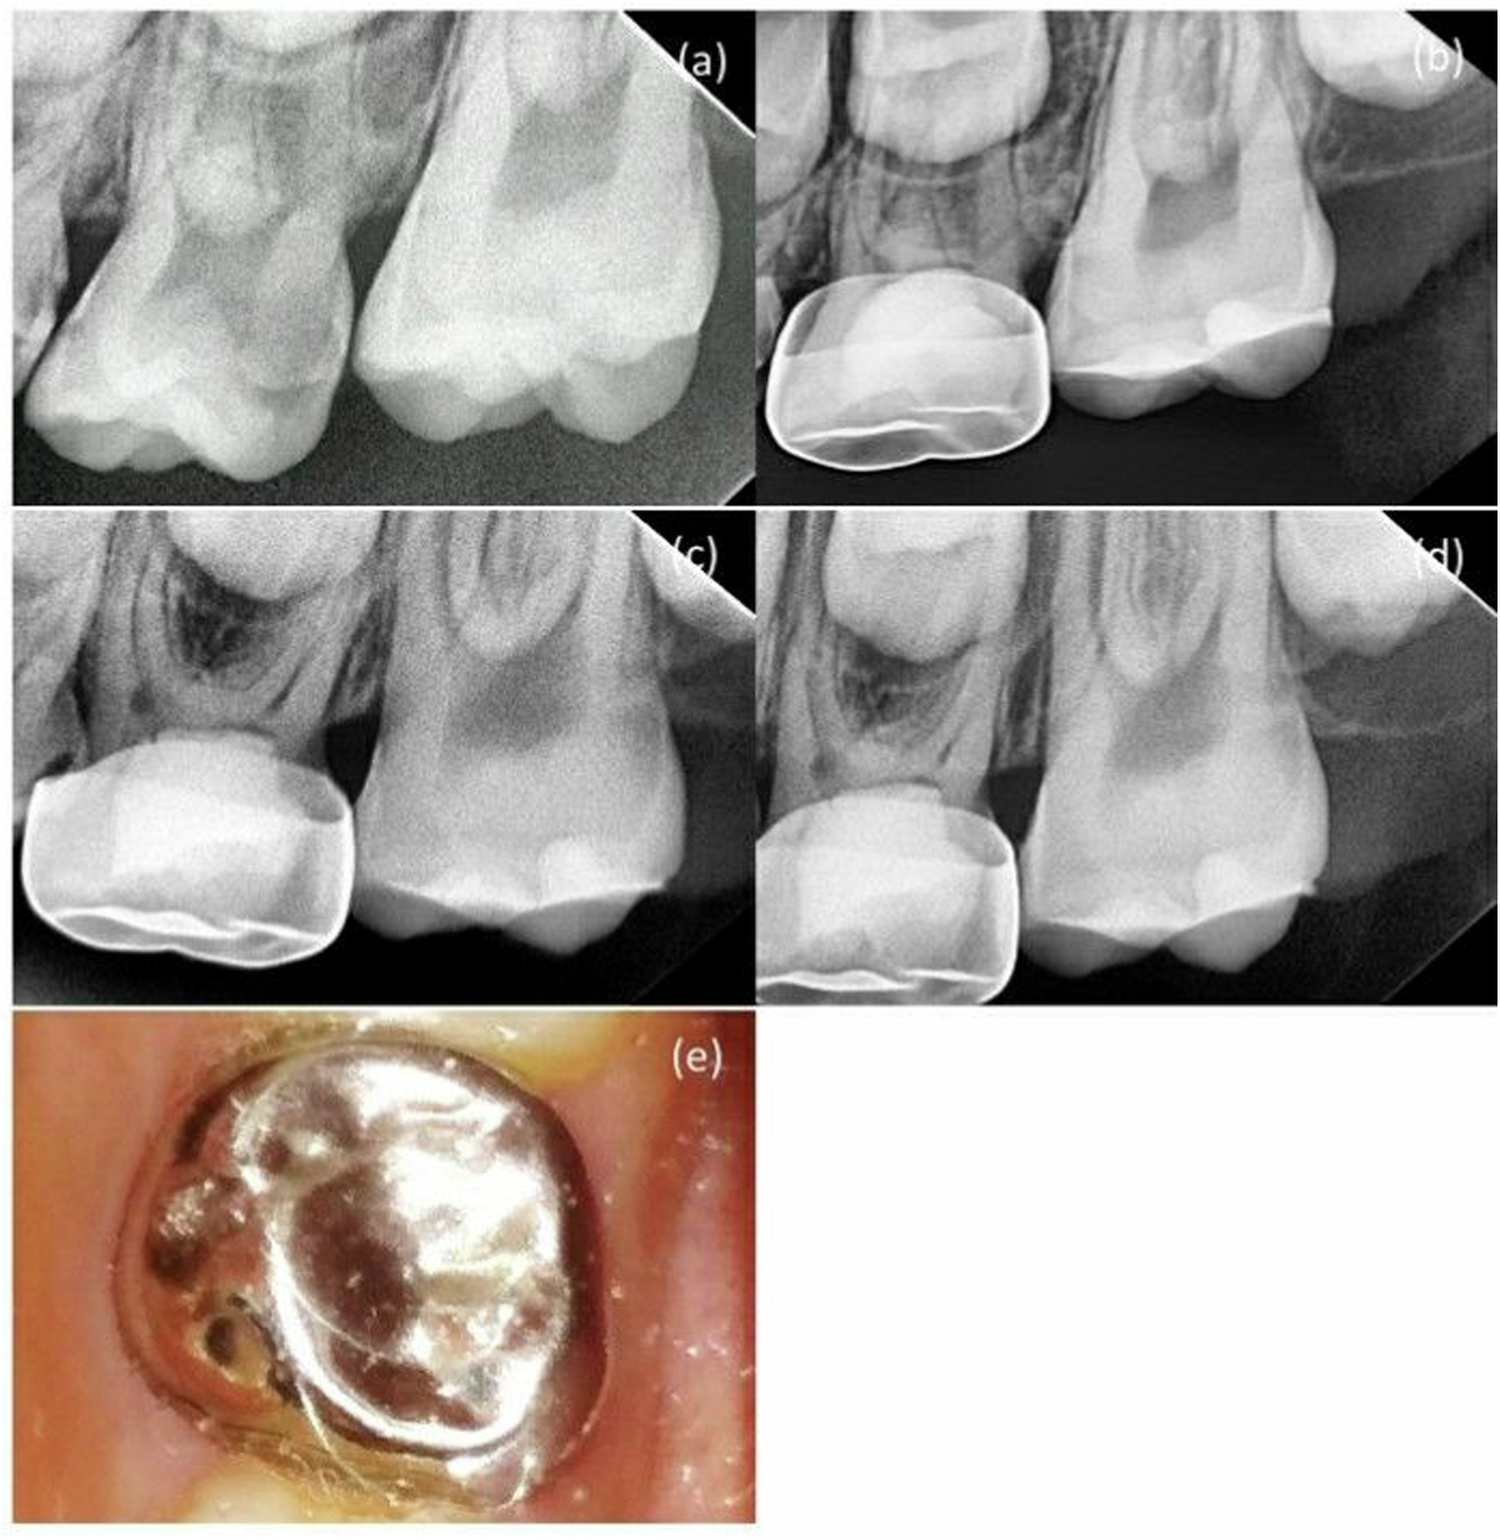

Fig. 4: MTA + DW group in second primary molar pulpotomy in a male participant aged 8 years.

a A preoperative radiograph. b 3-month follow-up. c 6-month follow-up. d 12-month follow-up. e A photograph after 12-month follow-up.